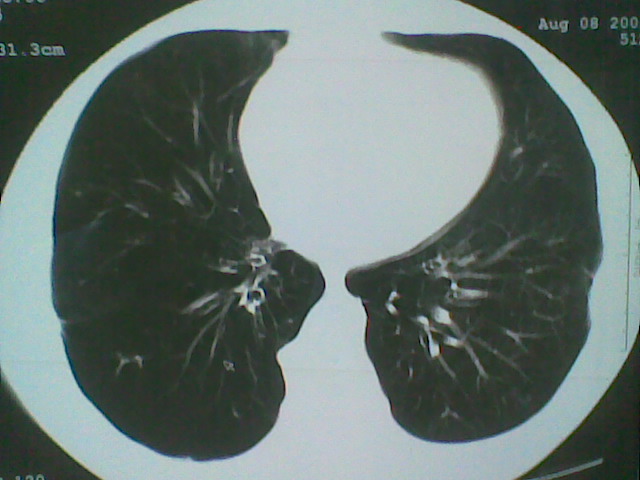

支持楼主意见,还有肺气肿

可以诊断为支扩。